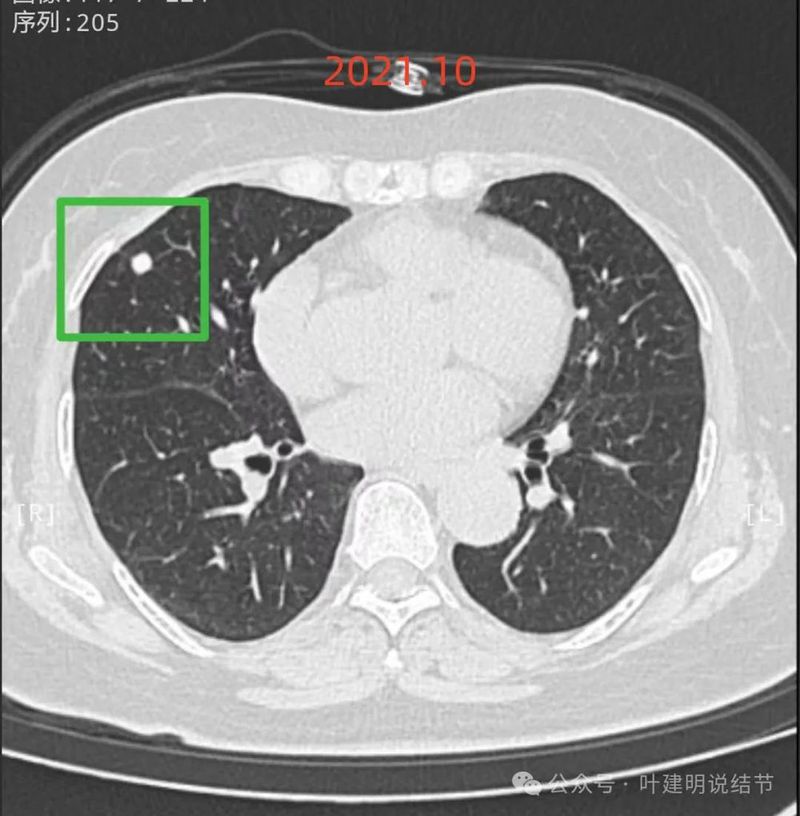

先看2021年10月时的影像:

右中叶实性结节,边缘光滑,毛刺不明显,考虑良性可能性较大。